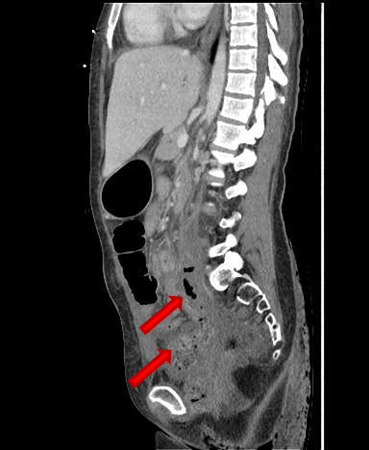

She presented on Emergency room suffering from fever, pelvic pain, and functional impairment of her right lower limb. Physical examination revealed bad smell vaginal flow and loss of strength on her right lower limb. Contrast computerized tomography and magnetic resonance images showed pelvic muscles impairment (Figure 1), inflamed bladder (Figure 2), and pelvic abscess lying from right psoas muscle to pubis bone, which presented radiologic signs of osteomyelitis (Figure 3) and (Figure 4).

Figure 3: CT scan image. Severe osteitis and osteomyelitis signs (cortical and medullary alteration) of bilateral pubic bones.

Figure 4: CT scan image. Severe osteitis and osteomyelitis signs (cortical and medulla alteration) of bilateral pubic bones.